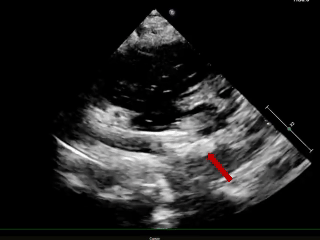

术后1周随访

超声报告:(1)房间隔封堵器位置正常,各瓣叶形态活动未见异常,右心比例稍大,左房室腔不大,心包腔内未见液性暗区; (2)多普勒检查:房水平未见残余分流;心功能:室壁运动协调,未见节段性异常;(3)先天性心脏病房间隔缺损封堵术后未见残余分流。